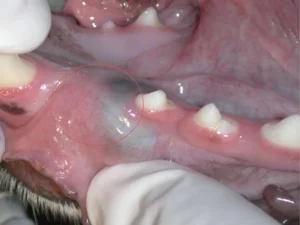

An area with an apparently missing tooth (circled above) began to show swelling. An x-ray of the area demonstrated a tooth that never erupted with an associated cyst. Because cysts may expand and cause damage to surrounding structures, oral surgery was performed to remove the entire cyst and unerupted tooth.